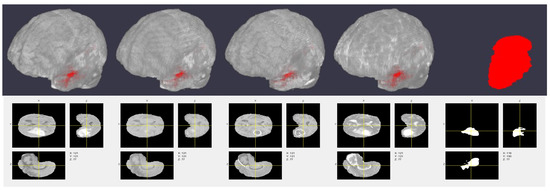

3.2.4. Comparison with Synthetic CT

Here, we evaluated the segmentation performance for the different MRI and synthetic CT combinations for input-level fusion, as it performed best in the previous experiment. Table 4 shows the results of this experiment, and Figure 7 visualizes some 3-D segmentation results. We observed that the combination of all five modalities performed best. This implies that our CT generation method was successful in providing additional information to supplement the segmentation task.

Figure 7. Example 3-D segmentation results. From top to bottom: ground truth labeled volume, predicted labeled volume, center slice of the ground truth labels, and center slice of the predicted labels. For the first and second columns, the brain volume was made transparent make the tumor region visible. The third and fourth columns represent the center slice of the ground truth and predicted labels along the depth direction.